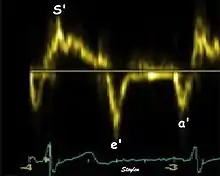

Annular velocities summarize the longitudinal contraction of the ventricle during systole, and elongation during diastole. Peak velocities are commonly used.

Systolic function

Peak systolic annular velocity (S') of the left ventricle is as close to a contractility measure as you can get by imaging[4] (bearing in mind that any imaging method only measures the result of fibre shortening, without measuring myocyte tension). S' has become a reliable measure of global function[5][6][7][8] It shares the advantage of annular displacement, that it is reduced also in hypertrophic hearts with small ventricles and normal ejection fraction (HFNEF), which is often seen in Hypertensive heart disease, Hypertrophic cardiomyopathy and Aortic stenosis.[9]

Diastolic function

As the ventricle relaxes, the annulus moves towards the base of the heart, signifying the volume expansion of the ventricle. The peak mitral annular velocity during early filling, e' is a measure of left ventricular diastolic function, and has been shown to be relatively independent of left ventricular filling pressure.[12][13][14] If there is impaired relaxation (Diastolic dysfunction), the e' velocity decreases. After the early relaxation, the ventricular myocardium is passive, the late velocity peak a' is a function of atrial contraction. The ratio between e' and a' is also a measure of diastolic function, in addition to the absolute values.

During the two filling phases, there is early (E) and late (A) blood flow from the atrium to the ventricle, corresponding to the annular velocity phases. The flow, is driven by the pressure difference between atrium and ventricle, this pressure difference is both a function of the pressure drop during early relaxation and the initial atrial pressure. In light diastolic dysfunction, the peak early mitral flow velocity E is reduced in proportion to the e', but if relaxation is so reduced that it causes increase in atrial pressure, E will increase again, while e', being less load dependent, remains low. Thus, the ratio E/e' is related to the atrial pressure, and can show increased filling pressure[15][16] although with several reservations.[17][18] In the right ventricle this is not an important principle, as the right atrial pressure is the same as central venous pressure which can easily be assessed from venous congestion.[19][20]